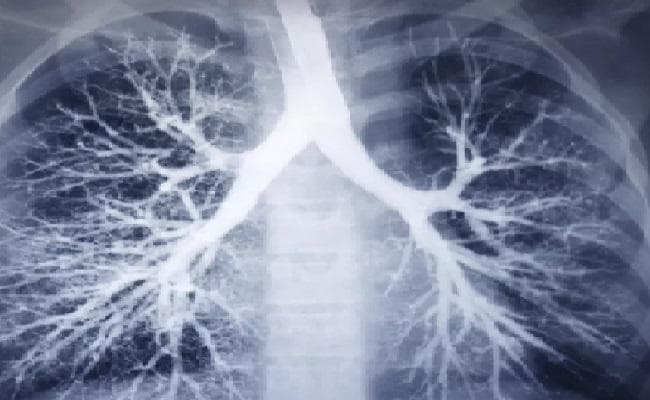

लंदन : विटामिन डी युक्त अनुपूरक आहार फेफड़े की बीमारी (सीओपीडी) से पीड़ित मरीजों में जानलेवा आघात के खतरे को कम कर सकता है. एक नये अध्ययन में ऐसा दावा किया गया है . ब्रिटेन की क्वीन मेरी यूनिवर्सिटी ऑफ लंदन के इस अनुसंधान ने विटामिन डी के स्वास्थ्य लाभों की सूची में एक और फायदा जोड़ दिया है.

साथ ही इसे कुपोषित बच्चों में वजन बढ़ाने एवं मस्तिष्क विकास के लिए भी सहायक बताया गया. अनुसंधान में पाया गया कि विटामिन डी अनुपूरक आहारों के इस्तेमाल से सीओपीडी मरीजों में फेफड़े का दौरा पड़ने की आशंका को 45 प्रतिशत तक घटाया जा सकता है. सीओपीडी मरीजों में विटामिन डी की कमी होती है . हालांकि जिन मरीजों में विटामिन डी का स्तर अधिक था उनमें कोई खास फायदा नहीं देखा गया. फेफड़े की बीमारियों से होने वाली लगभग सभी मौत फेफड़े का दौरा पड़ने से ही होती हैं. यह अध्ययन थोरेक्स पत्रिका में प्रकाशित हुआ है.